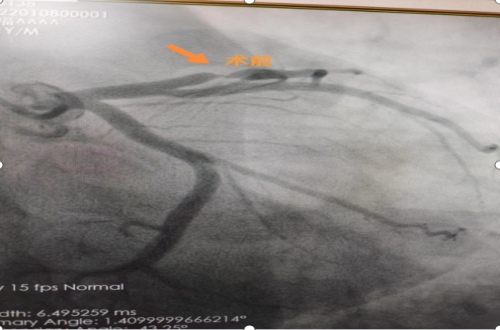

支架植入术前